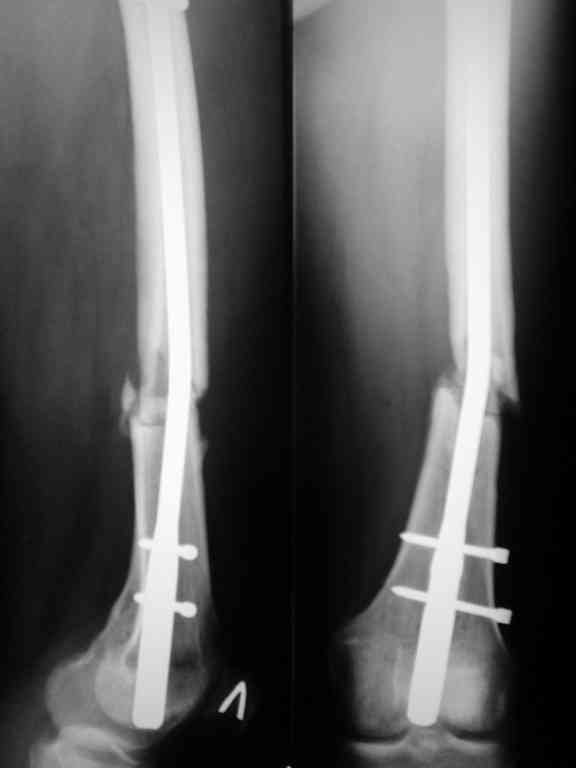

Соматически здорова. В ноябре 2004 года падение с высоты 12 м, перелом правой вертлужной впадины со смещением, неврит седалищного нерва, откр. перелом дистального отдела большеберцовой кости справа и закрытый перелом с/н/3 левого бедра. К нам поступила через 3 недели после травмы, был выполнен в 2 сессии сначала интрамедуллярный ретроградный остеосинтез бедра слева, затем остеосинтез вертлужной впадины и голеностопа справа. При остеосинтезе бедра пришлось немного приоткрыться в зоне перелома для репозиции и вообще операция затянулась часа на 2.5-3 (это один из наших первых интрамедуллярных синтезов). Через 4 месяца при нагрузке весом около 50 кг постепенно развилась варусная деформация бедра с искривлением стержня. Закрыто выпрямили под наркозом, динамизация гвоздя,но в сентябре 2005 г. согнулось бедро снова. Гвоздь удалили, остеосинтез пластиной, декортикация, пластика спонгиозой из метафиза б/берцовой кости. Динамика заживления вялая, но конструкция стояла неплохо (без признаков расшатывания), постепенно дали нагрузку - в марте 2006 года - перелом пластины - реостеосинтез пластиной, пластика гребнем подвздошной кости. На контролях (за август, т.е. 4 мес. после операции - прилагаю) динамика положительная, разрешена нагрузка до 50 кг. В начале этой недели без падения вновь появились боли в бедре - на Р-граммах - перелом пластины (снимки прилагаю). Фоном ко всему этому то, что и перелом вертлужки и дистального отдела б/б кости тоже не срастаются, хотя на голени уже дважды выполнялась костная пластика, на впадине - вторичное смещение, перелом части металлоконструкций. Исследовали гормональный фон - парат-гормон и прочие щитовидные в норме, месячные регулярно.Прошу совета по тактике дальнейшего лечения и выяснения причины тотального несращения всего сломанного.

Уважаемый Александр. Случай достаточно интересный, поскольку за 2 года,почему то ничего не срастается и все ломается. Жаль нет рентгенограмм таза и голени.Основными причинами несращения переломов бывает 1.не правильно выбранная тактика лечения, в том числе тактика оперативного лечения ( к примеру - не тот фиксатор, не того размера, неправильно установлен и т.д.)2.Девитализация костных отломков, а судя по рентгенограммам старались вы на совесть, когда открывали область перелома при интрамедуллярном остеосинтезе. Кстати, если это был не блокируемый остеосинтез, а обычный, то понятно почему стержень согнулся и нет сращения. На представленных рентгенограммах отдельные винты расположены даже с внутренней стороны, т.е. открылись вы качественно. 3.не правильно выбранная тактика лечения в п.операционном периоде или не выполнения больным данных рекомендаций. По бедру - мы бы убрали пластину и выполнили ретроградный блокируемый остеосинтез с рассверливанием. Если нет возможности, есть аппарат Илизарова. Но мороки и для вас и для больного много.

При первичном интрамедуллярном остеосинтезе применялся блокируемый гвоздь диаметром 9 мм ретроградно. У пациентки узкий костномозговой канал, поэтому были сложности (рассверливали долговато). Что касается разреза то его длина была 3-4 см не более. Т.е. насчет девитализации я согласен, но именно за счет рассверливания.

В приложении рентгенограмма бедра за авгутст 2005 с согнутым гвоздем и первичные.